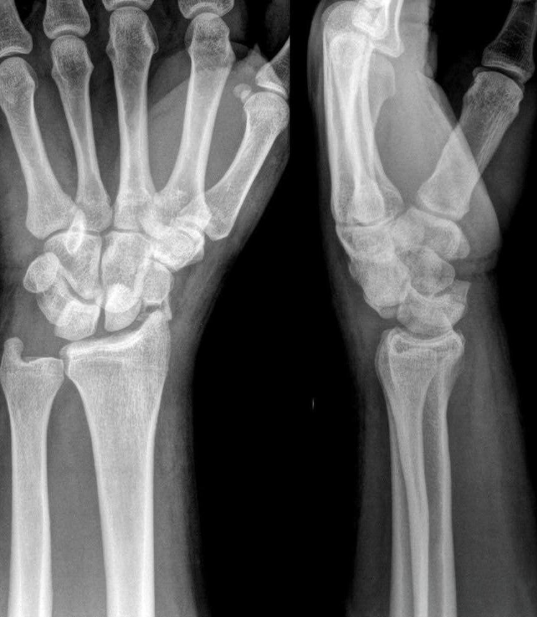

A 72-year-old woman presents to the emergency department with right wrist pain and swelling. She states that she was crossing the street when she fell and attempted to brace herself with her right hand.

Bent my bars and my wrist

A 32-year-old female presents to the ED for right wrist pain after a crash in a rock garden during a downhill mountain biking race. She has significant pain in her right wrist but denies any other pain or symptoms including numbness or tingling.

Tolerate More Than Pain

A 10-year-old male presents for right wrist pain after a fall while snowboarding. There is pain, swelling, and a deformity but he is neurovascularly intact.